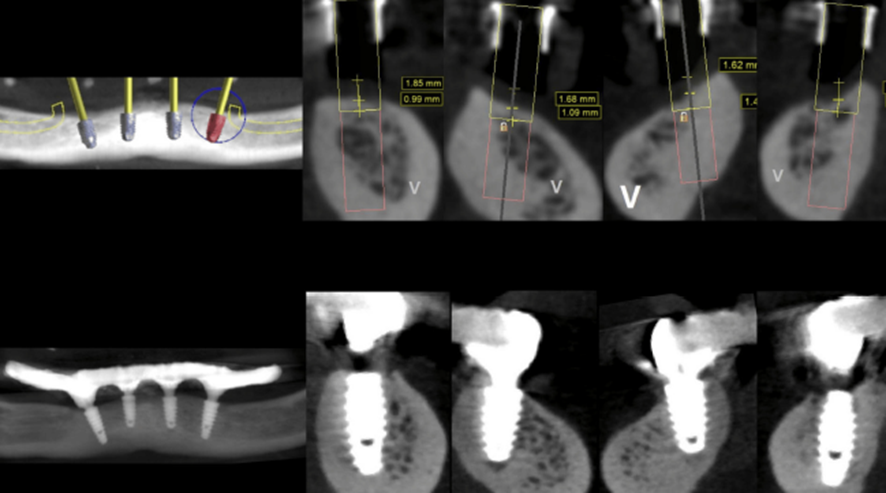

Em destaque na Matéria da Semana, apresentamos um caso clínico que envolve osteotomia, colocação de implante com carga imediata e cirurgia guiada e a instalação de uma prótese híbrida de resina impressa em 3D.

Todos os procedimentos foram planejados e realizados em ambiente computadorizado guiado. Além disso, os implantes utilizados neste estudo apresentaram uma conexão cônica e modificações de superfície projetadas para aprimorar a osseointegração e a estabilidade biomecânica. A macrogeometria dos implantes utilizados facilita a estabilidade primária em osso mandibular denso, enquanto o conceito de plataforma switching ajuda a preservar a crista óssea.

A novidade neste caso envolveu o uso de fluxo de trabalho digital, um guia cirúrgico empilhável personalizado de três partes e uma prótese provisória impressa feita de resina.